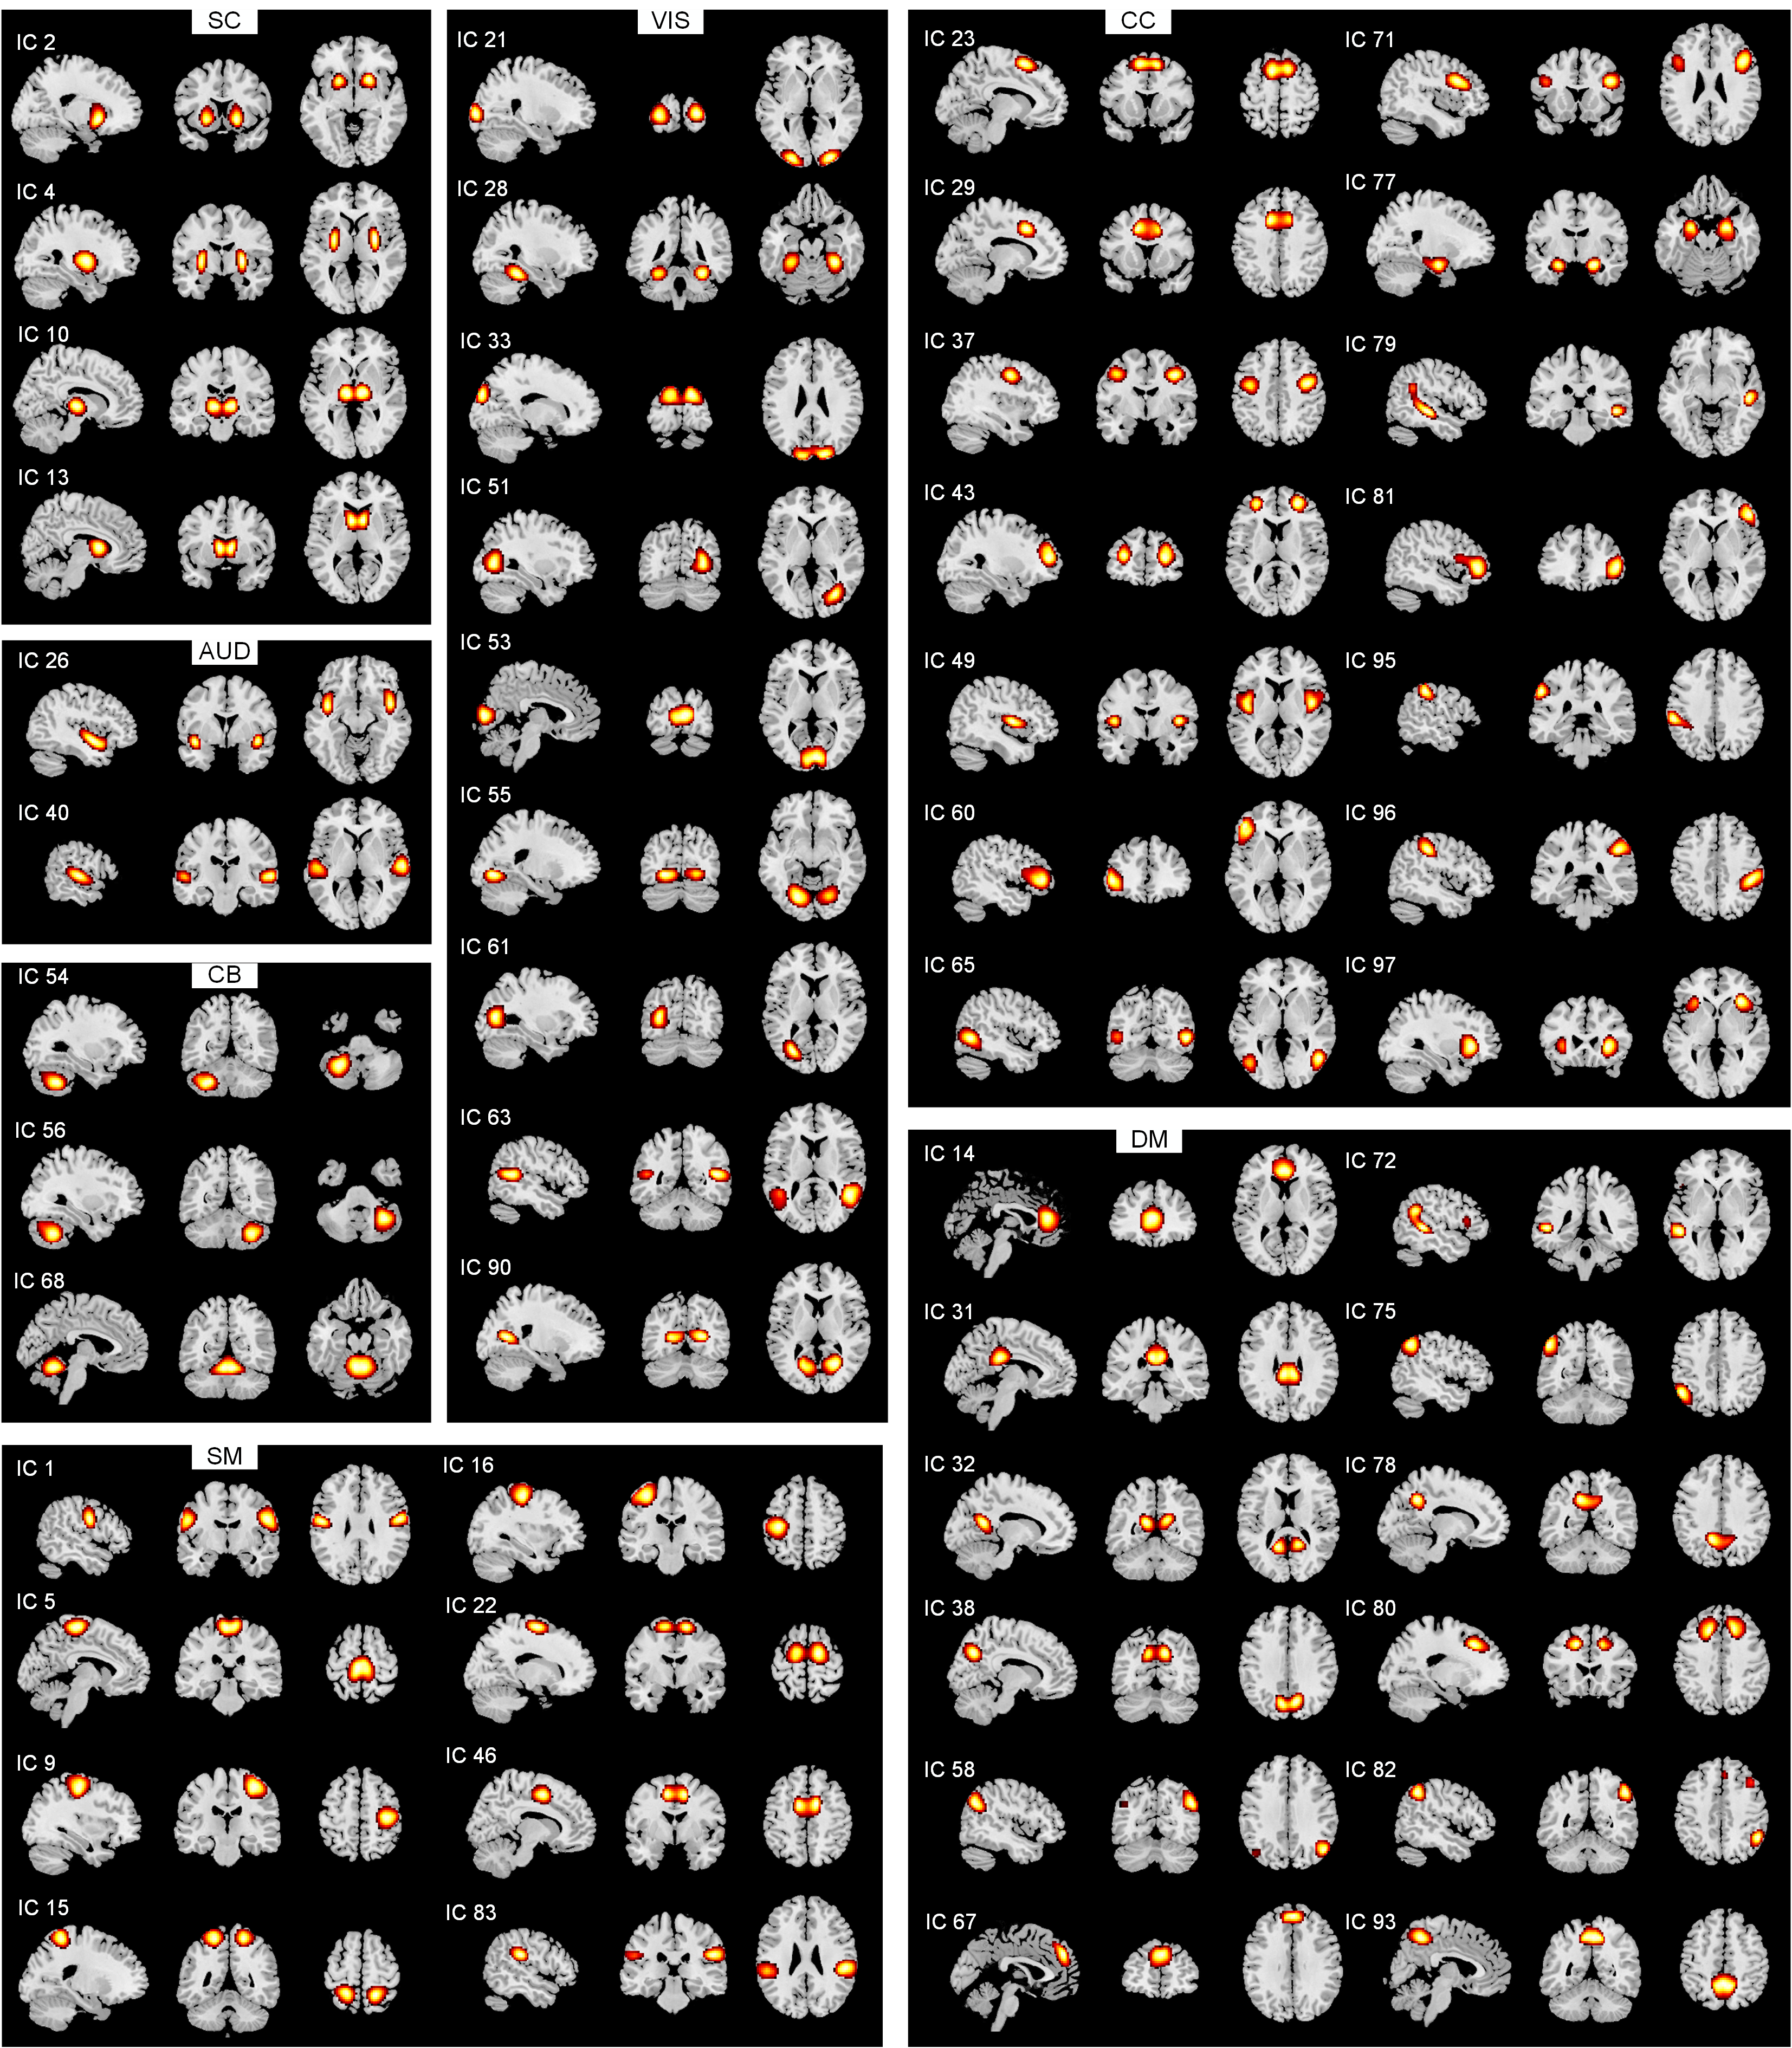

| 图1 7网络中的52个IC的空间图(空间图阈值为t > µ + 5σ) |

| Fig. 1 Spatial maps for the 52 independent components grouped into seven functional networks (spatial maps were thresholded with t > µ + 5σ) |